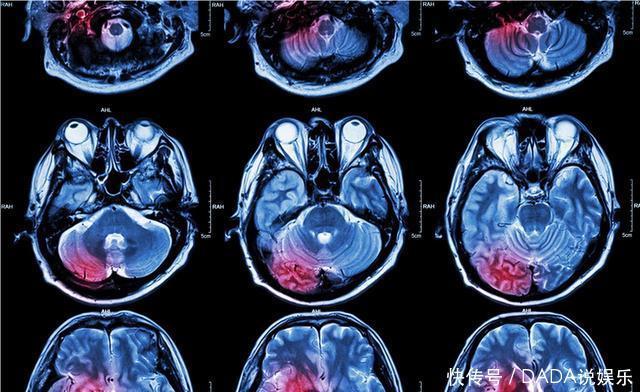

科学家发现人死后大脑中出现大量未知活动